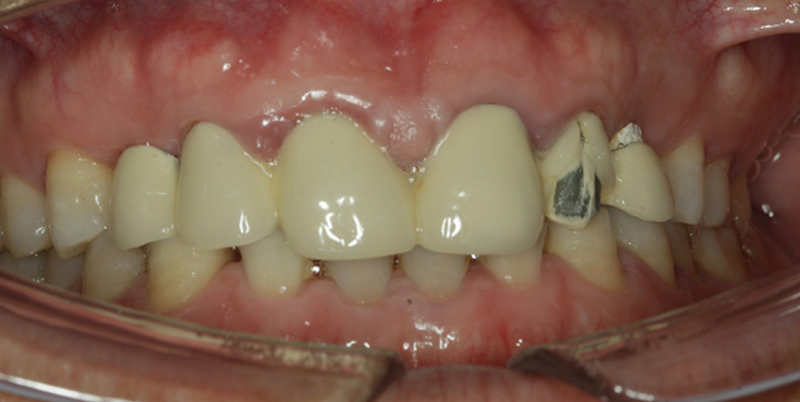

檢查:22烤瓷牙表面崩瓷,13、23、24缺失

診斷:患者13、23、24缺失,上頜竇囊腫明顯,23、24頰側(cè)牙槽骨吸收嚴(yán)重

1、不良修復(fù)體松動脫落,崩瓷;

2、深覆合;

3、牙齦炎。